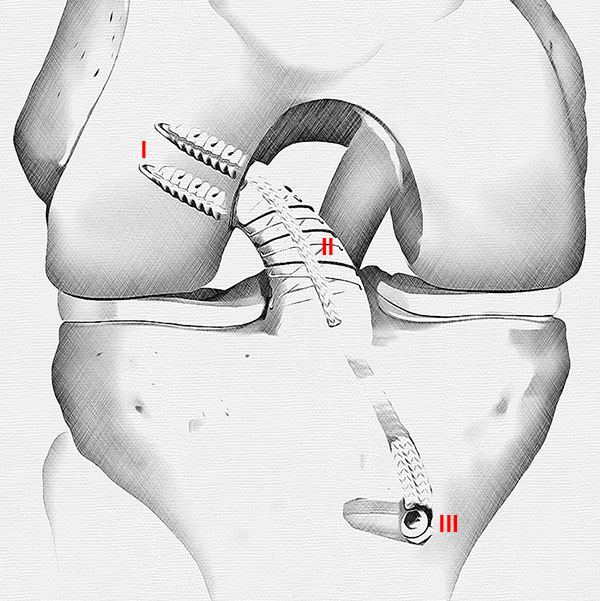

En un estudio reciente, con una técnica combinada, igual a la que describimos en nuestro reporte de caso (fig. 7), evaluó los resultados y el papel del aumento adicional con refuerzo interno (internal brace) en una cohorte más grande de 56 pacientes, las tasas de re-ruptura fueron del 7,4% y del 13,8% sin refuerzo interno (P = 0,672). No hubo diferencias estadísticamente significativas o clínicamente relevantes en los resultados subjetivos.54

Figura 7: Dibujo que muestra el resultado final con la técnica de reparación primaria artroscópica con fijación femoral independiente de cada haz con 2 anclajes ventados BioCompuestos SwiveLock de 4,75 mm (Arthrex) aumentado con Tigertape 2mm (Arthrex) como internal brace fijado en la tibia con un anclaje SwiveLock de 4,75 mm. I: SwiveLock 4.75 mm. II: TigerTape 2mm (Internal Brace). III: SwiveLock 4.75 mm.